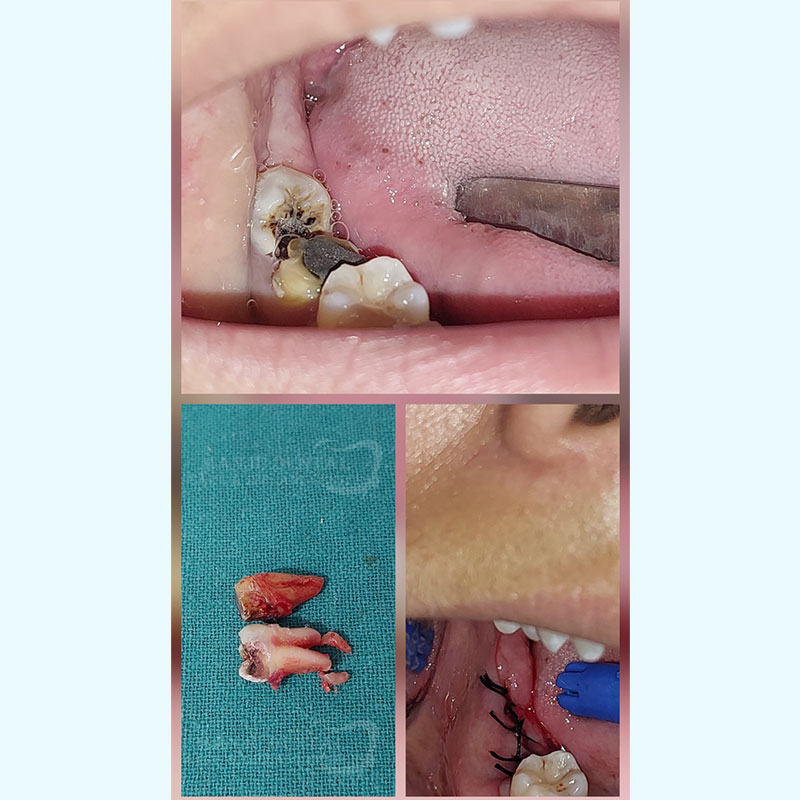

Surgical Extraction of Impacted Lower Wisdom Tooth

Surgical Extraction of Grossly Carious Molars